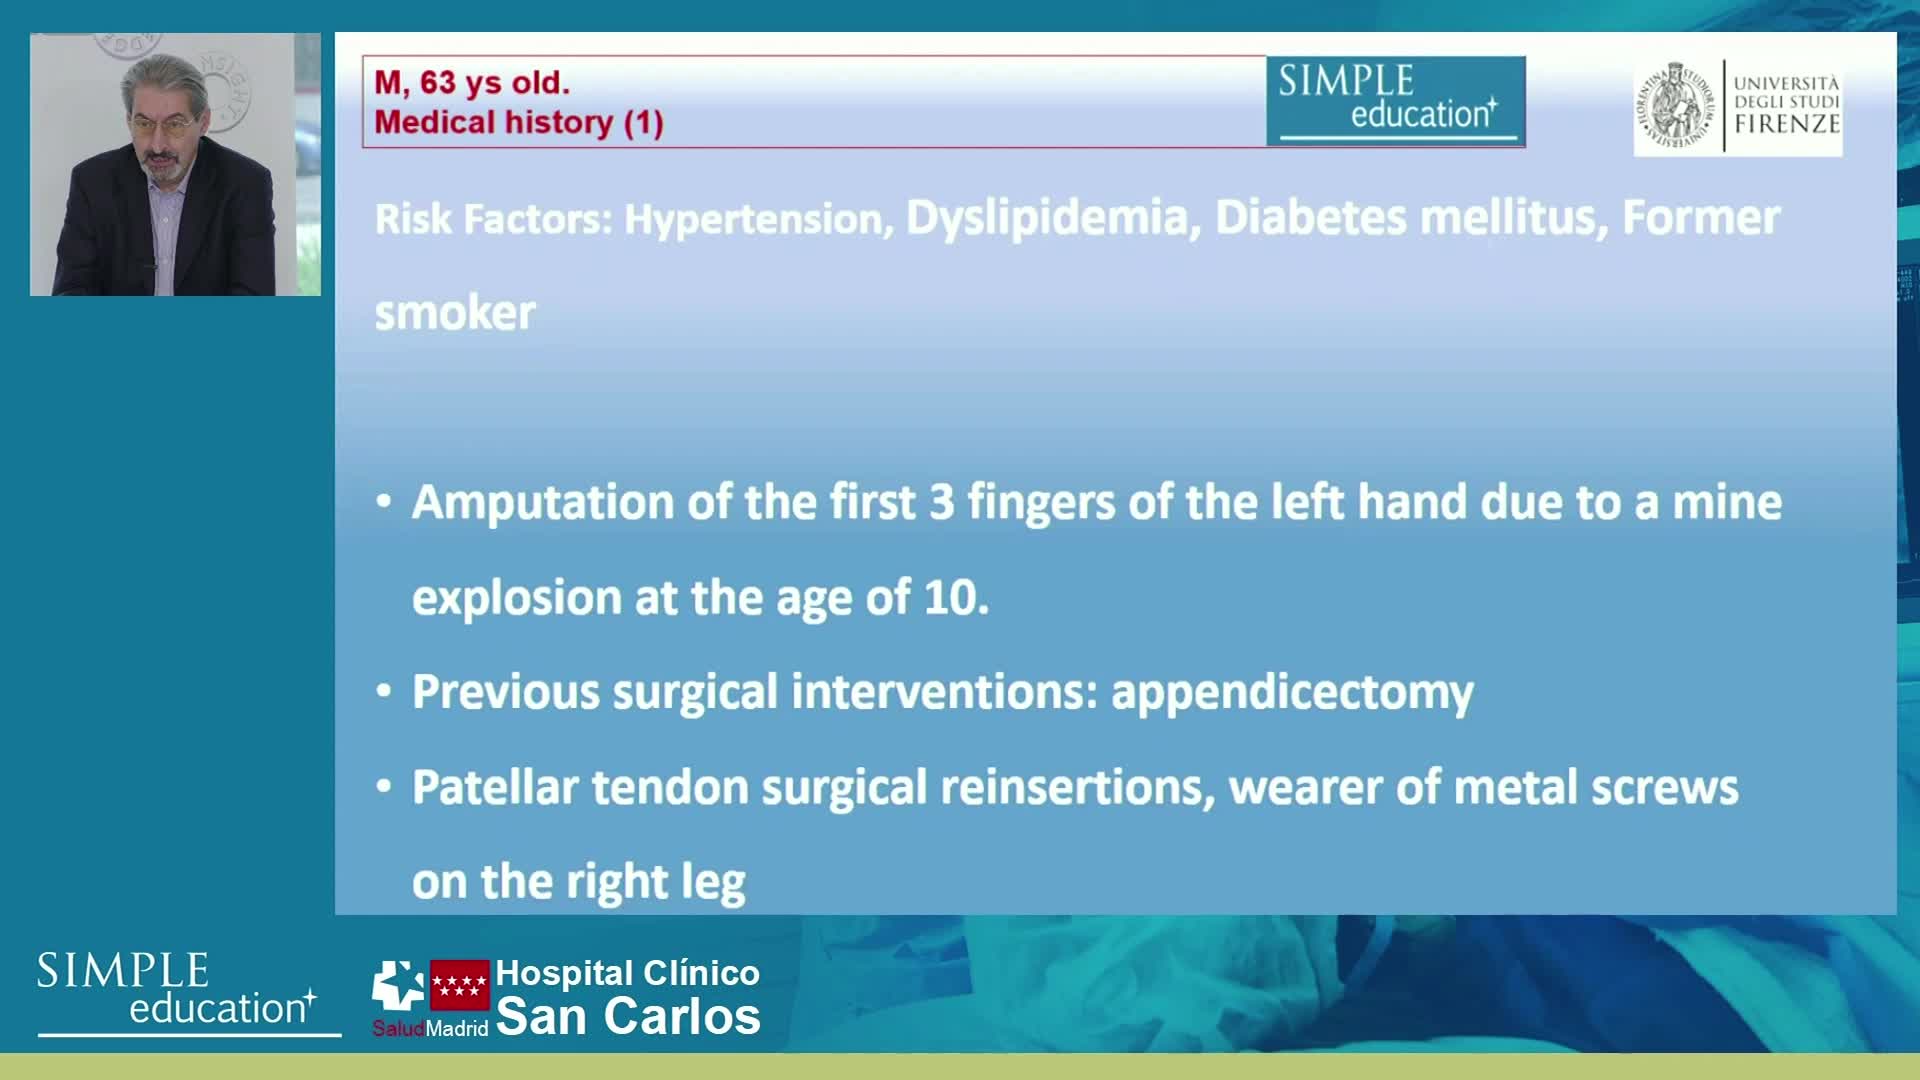

Best practices and personalised medicine in complex PCI - Prof Javier Escaned

Essential steps for physiology-based PCI planning and guidance - Dr Allen Jeremias

Intracoronary guidance in acute coronary syndromes - Dr Hernan Mejia-Renteria

Coronary Bifurcations: An Update on Diagnosis, PCI planning and Imaging and PhysiologyGuidance - Dr Dejan Milasinovic